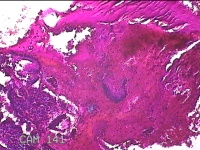

宫颈管内膜组织

性别

女

年龄

39岁

临床诊断

子宫异常出血 子宫内膜不典型增生?子宫内膜占位性病变待查 慢性宫颈炎

一般病史

阴道流血3天,增多1小时。

标本名称

大体所见

灰白暗红色不规则碎组织1.8x1.3x0.3cm一堆。

子宫颈管内膜和子宫内膜组织,没有什么大问题。